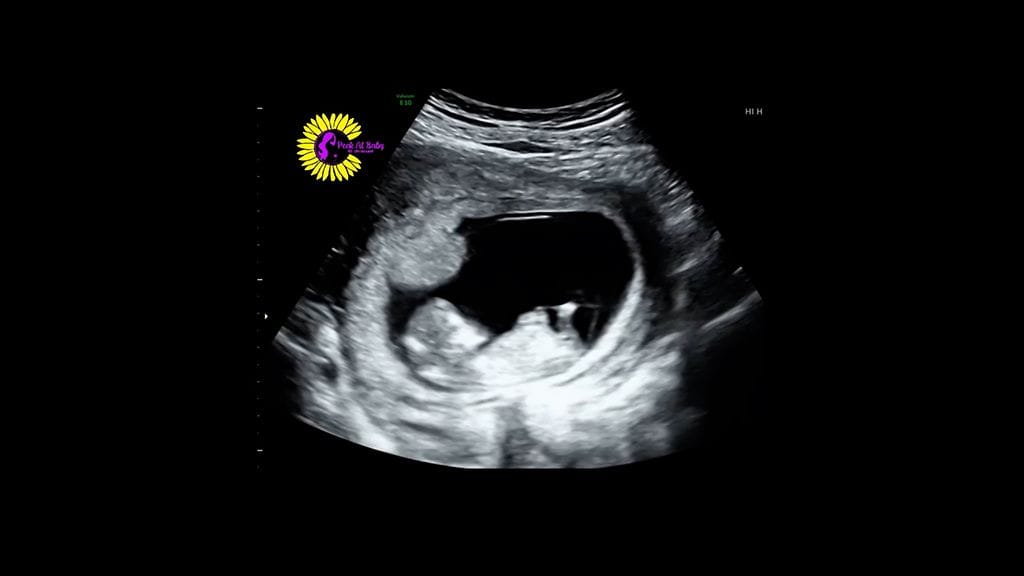

Äiti purskahti neuvolassa hillittömään nauruun – sitten ultraäänessä tapahtui jotain yllättävää

Äidin naurunpuuska muuttui hillittömäksi naurukohtaukseksi, kun ultraääni paljasti, mitä äidin kohdussa tapahtui.